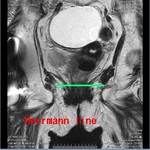

[画像診断]様々な背景における肺炎の起炎菌について 2011-05-25